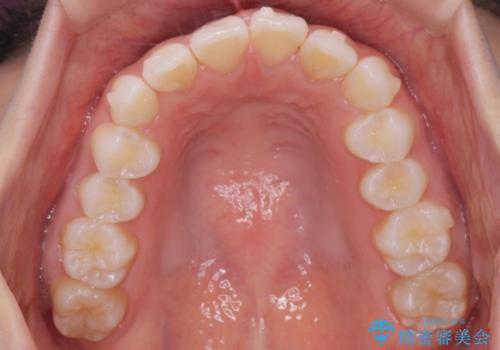

前歯のがたつき気になる。インビザラインモデレート

- 前歯のがたつきが気になるとの事で来院。

噛み合わせを確認したところ上の歯が全体的に前にある状態でした。

患者様は2のプランを選ばれたのでインビザラインモデレートで治療を行いました。

ガタつきがなくなり満足して頂けました。